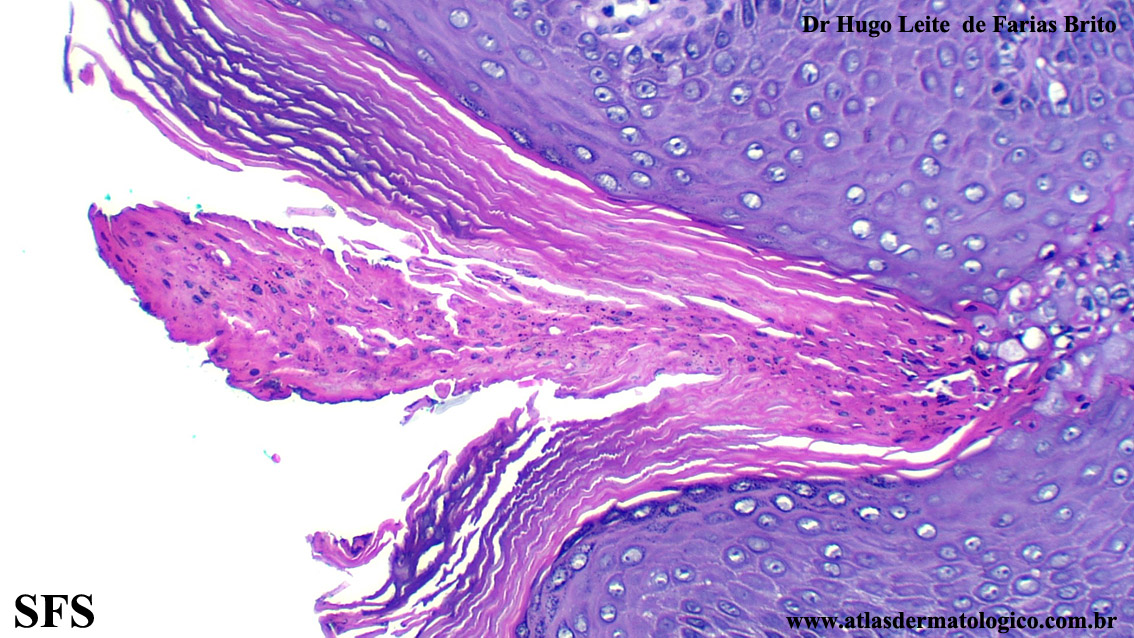

porokeratosis-inguinal_porokeratosis